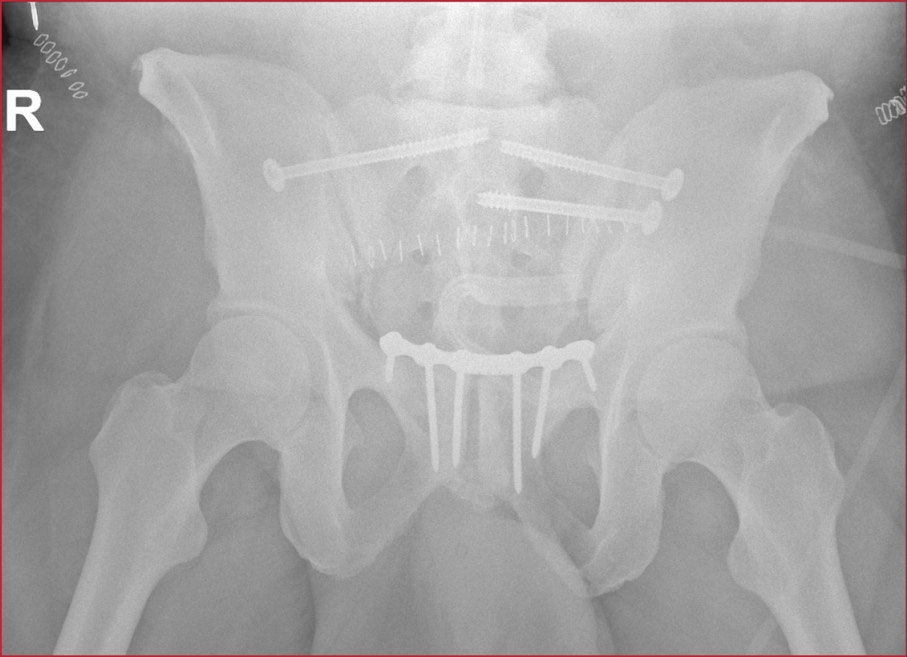

Hombre de 43 años, sin antecedentes personales de interés, que ingresa en nuestra Unidad, tras sufrir un traumatismo pélvico repetitivo con el cuerno o la perilla de la montura en la doma de caballo. El paciente es trasladado al Servicio de Urgencias hospitalario con incapacidad para deambular y dolor intenso. Se realiza una tomografía computarizada abdomino-pélvica de urgencia, que muestra una fractura inestable de pelvis tipo C2 de la clasificación de Tile, en libro abierto, con diástasis de la sínfisis púbica de 9,5 cm (Figura 1, flecha), articulación sacroilíaca izquierda y derecha (Figura 2, flechas), asociada con hematoma de partes blandas en el pubis y la región ilíaca izquierda, y sangrado activo en dicha zona. Se procede a la fijación externa urgente a cargo del equipo de guardia de Traumatología y se lo traslada a la Unidad de Cuidados Intensivos, donde posteriormente es sometido a fijación y osteosíntesis del anillo pélvico (Figura 3, flecha).

Figura 3. Radiografía tras la fijación y osteosíntesis del anillo pélvico.